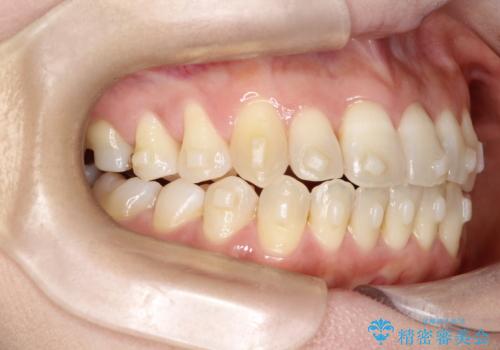

【開咬】笑った時の見た目を改善したい。

- 重度の開咬でしたがインビザラインで適切に治療計画を立て、きれいに仕上がりました。

インビザラインは開咬の治療に向いています。